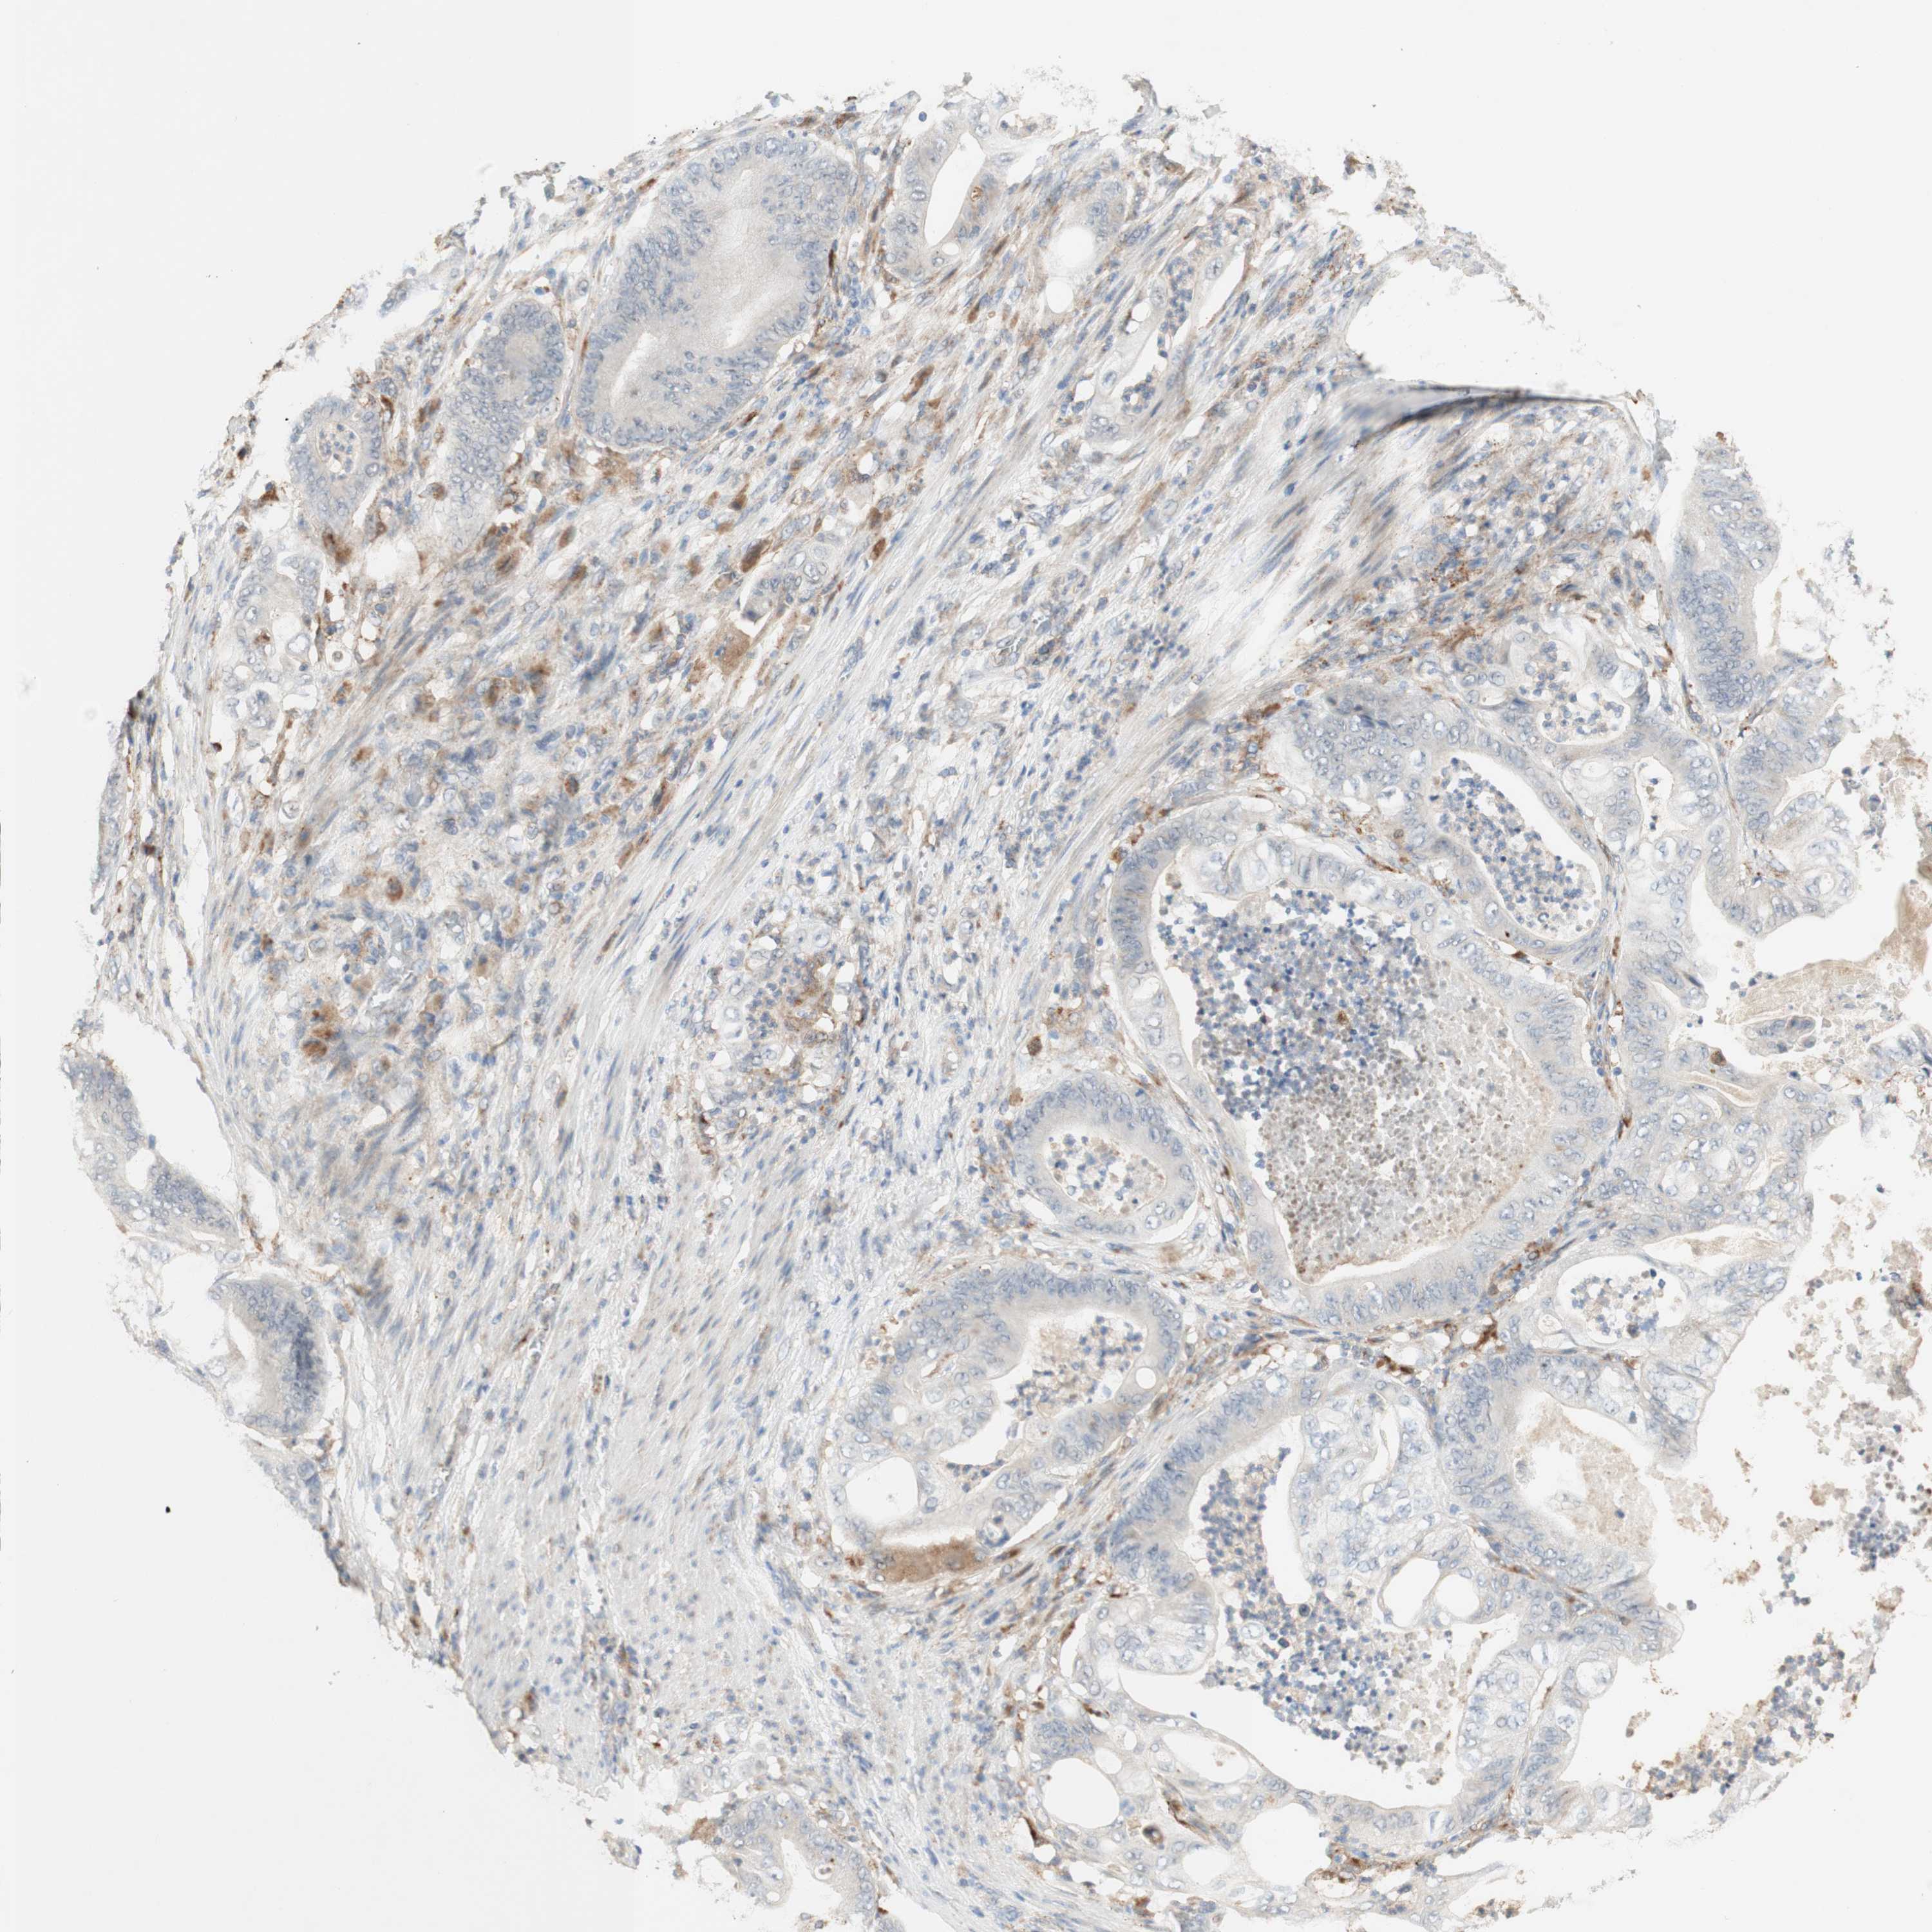

STOMACH CANCER - Protein expressioni

A mouse-over function shows sample information and annotation data. Click on an image to view it in a full screen mode. Samples can be filtered based on level of antibody staining by selecting one or several of the following categories: high, medium, low and not detected. The assay and annotation is described here.

Note that samples used for immunohistochemistry by the Human Protein Atlas do not correspond to samples in the TCGA dataset.

Antibody stainingi

Antibody staining in the annotated cell types in the current human tissue is reported as not detected, low, medium, or high, based on conventional immunohistochemistry profiling in selected tissues. This score is based on the combination of the staining intensity and fraction of stained cells.

Each image is clickable and will lead to virtual microscopy that enables deeper exploration of all samples and also displays staining intensity scores, fraction scores and subcellular localization as well as patient and tissue information for each sample.

Antibody HPA011070

Staining

High

Medium

Low

Not detected

Intensity

Strong

Moderate

Weak

Negative

Quantity

>75%

75%-25%

<25%

None

Location

Nuclear

Cytoplasmic/membranous

Cytoplasmic/membranous,nuclear

Adenocarcinoma, NOS

Adenocarcinoma, High grade